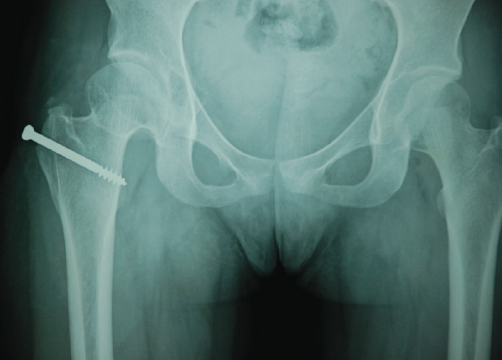

Primary Synovial Chondromatosis of the Hip Joint: A Case Report

Madhan Jeyaraman , Naveen Jeyaraman , Swaminathan Ramasubramanian , Arulkumar Nallakumarasamy